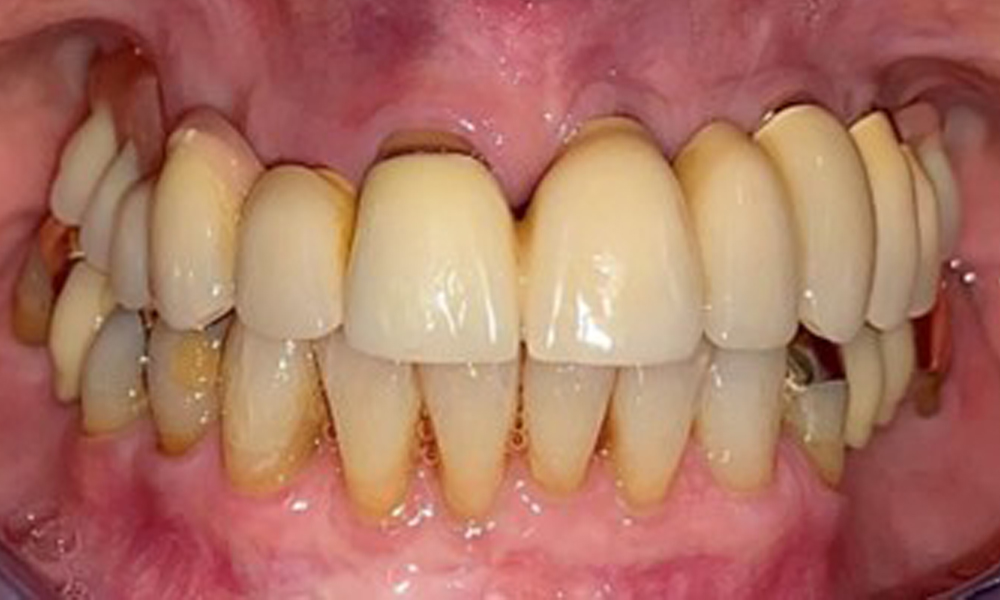

Die Patientin wurde vor über 25 Jahren mit einer kombinierten herausnehmbare Implantat-Teleskopprothese im Oberkiefer versorgt (Abb. 1, Abb. 2, Abb. 3) und ist sehr glücklich über ihren Zahnersatz. Im Unterkiefer hat die Patientin einen suffizienten festsitzenden Zahnersatz. (Abb. 4)

Frontalansicht mit dem eingesetzten Zahnersatz im Oberkiefer.

Abb. 1: Frontalansicht mit dem eingesetzten Zahnersatz im Oberkiefer.